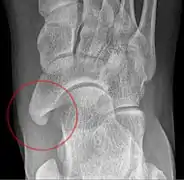

Radiological images

From left to right: Type 1, 2 and 3

Lateral projection of type 2